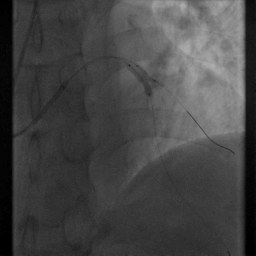

右冠优势型冠脉,LM(-),LAD近段粗大,内膜不光滑

D1开口后管状狭窄,狭窄最重90%,D1开口狭窄40-50%,前向血流TIMI Ⅲ级

LCX内膜不光滑,前向血流TIMI Ⅲ级

RCA内膜不光滑,前向血流TIMI Ⅲ级

造影结果显示:对角支发出后狭窄90%,狭窄前后血管直径相差大